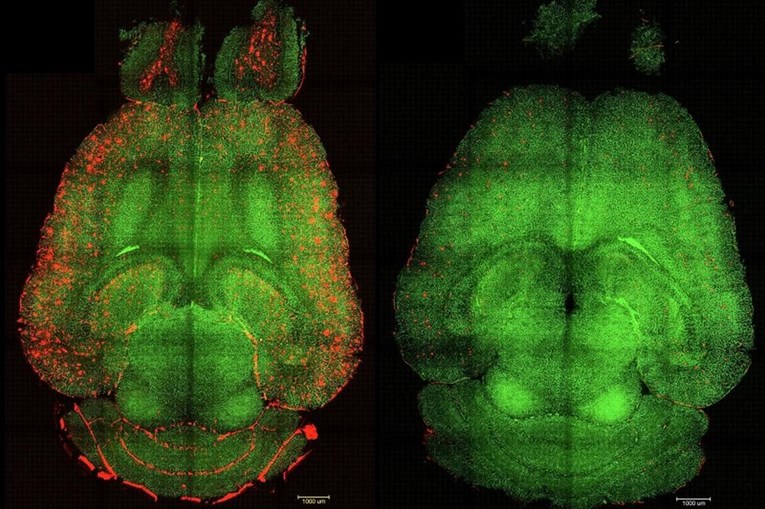

U nizu eksperimenata na genetski modificiranim miševima, koji proizvode velike količine amiloid-beta proteina i pokazuju pad kognitivnih funkcija, primjena supramolekularnih lijekova dovela je do gotovo trenutačnog smanjenja razine tog proteina. "Samo jedan sat nakon injekcije, primijetili smo smanjenje količine amiloid-beta proteina u mozgu za 50-60 posto", izjavio je koautor i istraživač iz Bolnice Zapadne Kine Sveučilišta Sichuan.

Posebno je uzbudljivo otkriće da su kognitivna poboljšanja kod miševa bila značajna. Miš, čija bi dob bila ekvivalent 90-godišnjeg čovjeka, "povratio je ponašanje zdravog miša" šest mjeseci nakon primanja tretmana. "Dugoročni učinak proizlazi iz obnove vaskulature mozga", objasnio je Battaglia.